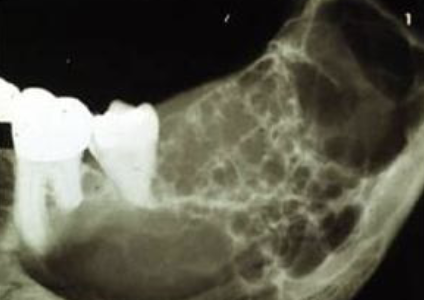

Radiographic Shape : multiple single-chambered lesions that are somewhat fused together, making up the entire lesion; sometimes described as resembling soap bubbles

multilocular